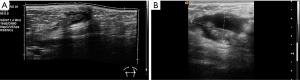

US findings of tendinous and muscular lesions injuries include disruption, absence and retraction of the tendon and muscle fibres, as well as haematoma. Immediately after injury, a haemorrhage is hypoechoic; however, it will become heterogeneously echogenic with clot formation and organization into a haematoma.

The pectoralis major is the most superficial of the anterior scapular muscles. It originates on the clavicle, sternum, rectus sheath, and on the costal cartilages of the first six ribs, inserting on the lateral lip on the bicipital groove. The frequency of injuries of the pectoralis major muscle has been increasing during the past two decades (30). This trend can be attributed in part to increasing cases of sports-related trauma and the growing popularity of weight-training regimens such as bench press weight-lifting exercises. Patients are generally young and active. The most common mechanism of injury is excessive tension on a maximally contracted muscle (31). Injuries of the pectoralis major can be categorized according to their location: muscle origin or belly, musculotendinous junction, intratendinous region, humeral insertion, or area of bone avulsion at the humeral attachment. Most of pectoralis major injuries occur at the humeral insertion (59%) and musculotendinous junction (24%) (32). Patients with injuries at the muscle origin or belly, including contusions and strains, usually are treated conservatively. Injuries involving bone avulsion at the humeral attachment may benefit from a primary fracture fixation (33).

A normal pectoralis major tendon should have uniform low signal intensity on MR imaging. Like US (34), tears of the pectoralis major tendon seen on MR imaging exhibit different degrees of tendon abnormality, depending on the degree of injury. A grade I strain of the muscle belly will have feathery intramuscular fluid-sensitive signal intensity, which represents oedema and/or haemorrhage. Grade II injury will appear as a partial tear with an intramuscular hematoma, while grade III injury has a complete tear with possible retraction (Figures 11-13). As a matter of fact, a partial tear involving only the posterior sternal segments, the anterior clavicular head and tendon will be intact, with the long head of the biceps tendon in place. With complete tears involving both the sternal head and the clavicular head, however, there will be disruption of the entire tendon, with anterior displacement of the long head of the biceps tendon (35).